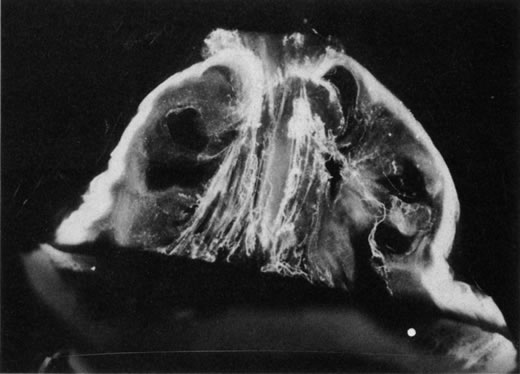

The retina is usually not involved in anterior PHPV. Indeed, previous studies have suggested that the anterior form is due to a primary defect in lens development and that vitreous changes are all secondary.34 This postulate has never been substantiated. There are rare instances of posterior PHPV in which opaque connective tissue arises from Bergmeister's papilla and persistent hyaloid vessels (Fig. 1).32,35 These can cause congenital falciform folds of the retina and, if severe, can cause tentlike retinal folds, leading on rare occasions to tractional and/or rhegmatogenous retinal detachment. Font and investigators36 demonstrated the presence of adipose tissue, smooth muscle, and cartilage within the retrolental plaque and suggested that PHPV arises from metaplasia of mesenchymal elements in the primary vitreous.